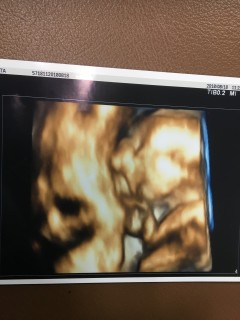

今日は胎児スクリーニング検査で、心臓や脳などに異常がないかの検査でしたが、今のところ何も問題なく元気な赤ちゃんでした。 373gとの事でした。性別も女児確定を頂きました! 初めての4Dエコー、本当に感動。あんなお豆みたいだった赤ちゃんがここまで成長してるとは…。もう可愛すぎて親バカまっしぐらです。